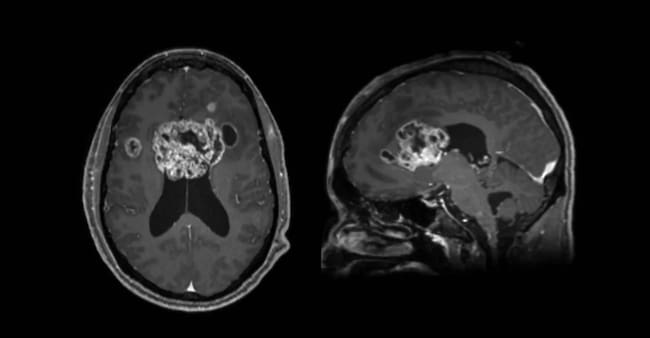

Su esposo, Brunson Green, recordó el hallazgo en urgencias: “Fuimos a urgencias y en cinco minutos nos dijeron que tenía un bulto del tamaño de una pelota de béisbol en medio del cráneo”.

El glioblastoma, descrito por el propio Collins como “una mariposa que prácticamente lo invadió todo”, se expandió con rapidez, complejizando rápidamente las cosas y dejando poco tiempo de reacción.

Tras radioterapia, el tumor duplicó su tamaño en dos o tres semanas, pese a un pronóstico estándar de 11 a 14 meses de supervivencia, siendo un remezón para la familia.